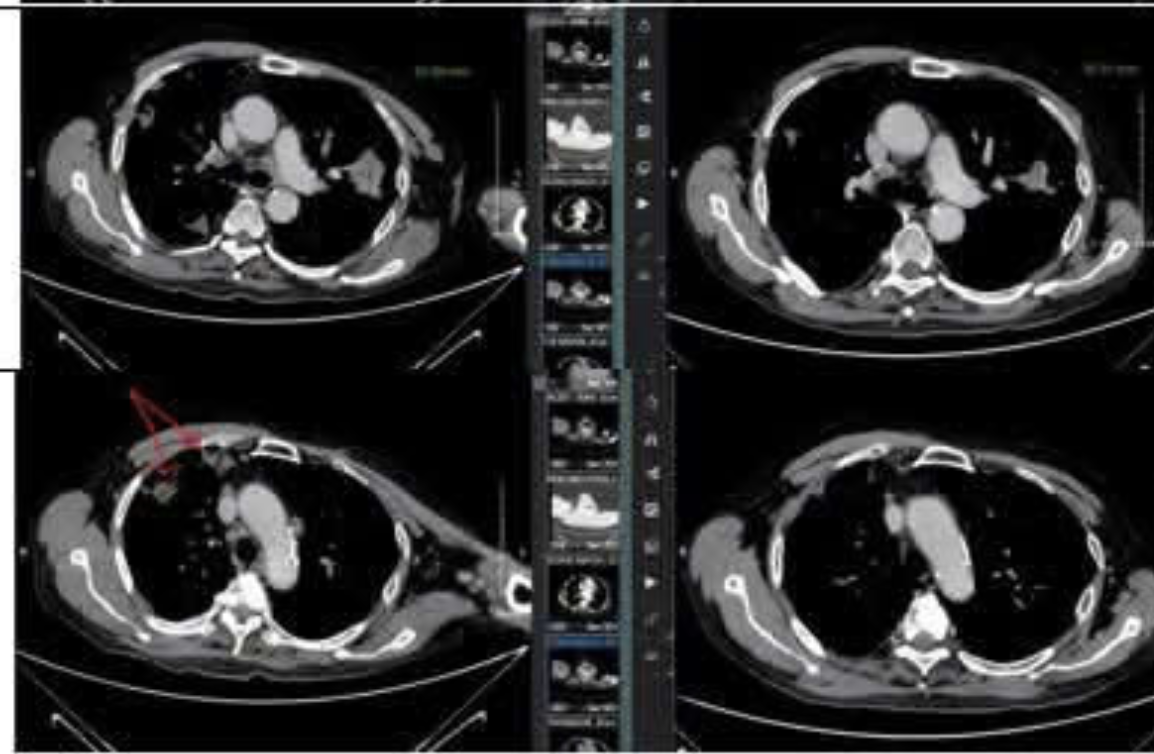

Mới đây, Thạc sĩ, bác sĩ Nguyễn Duy Anh, Trung tâm Ung bướu, Xạ trị và Y học hạt nhân Quốc tế, Bệnh viện Đa khoa Phương Đông, chia sẻ về trường hợp một bệnh nhân mắc ung thư phổi giai đoạn cuối kiên trì làm 1 điều giúp khối u thu nhỏ 50%.

Theo đó, bệnh nhân là một người đàn ông ngoài 60 tuổi, phát hiện ung thư phổi giai đoạn cuối vào khoảng một năm trước, khi tế bào ung thư đã lan lên não. Kết quả xét nghiệm cho thấy bệnh nhân có đột biến gen EGFR – cho phép sử dụng thuốc nhắm trúng đích, được ví như “viên đạn thông minh” tấn công trực tiếp tế bào ung thư.

Bệnh nhân được điều trị kết hợp: xạ phẫu Gamma Knife cho tổn thương di căn não và uống thuốc đích thế hệ mới hàng ngày. Suốt gần một năm, bệnh nhân duy trì tình trạng ổn định. Tuy nhiên, đến đầu năm 2025, trong lần tái khám định kỳ, bác sĩ phát hiện các tổn thương mới ở não và khối u tại phổi phát triển nhanh chóng khiến bệnh nhân liệt nửa người trái.

Sau ba chu kỳ hóa trị (hơn 2 tháng), điều bất ngờ đã đến: Khối u tại phổi giảm kích thước đến 50%, nhiều tổn thương di căn ở não biến mất hoặc thu nhỏ đáng kể.

Kết quả điều trị này khiến cho cả bệnh nhân và bác sĩ đều “vỡ oà” hạnh phúc. Bệnh nhân bắt đầu cử động được tay chân bên trái, ăn ngủ tốt hơn, tinh thần cũng dần phấn chấn trở lại.